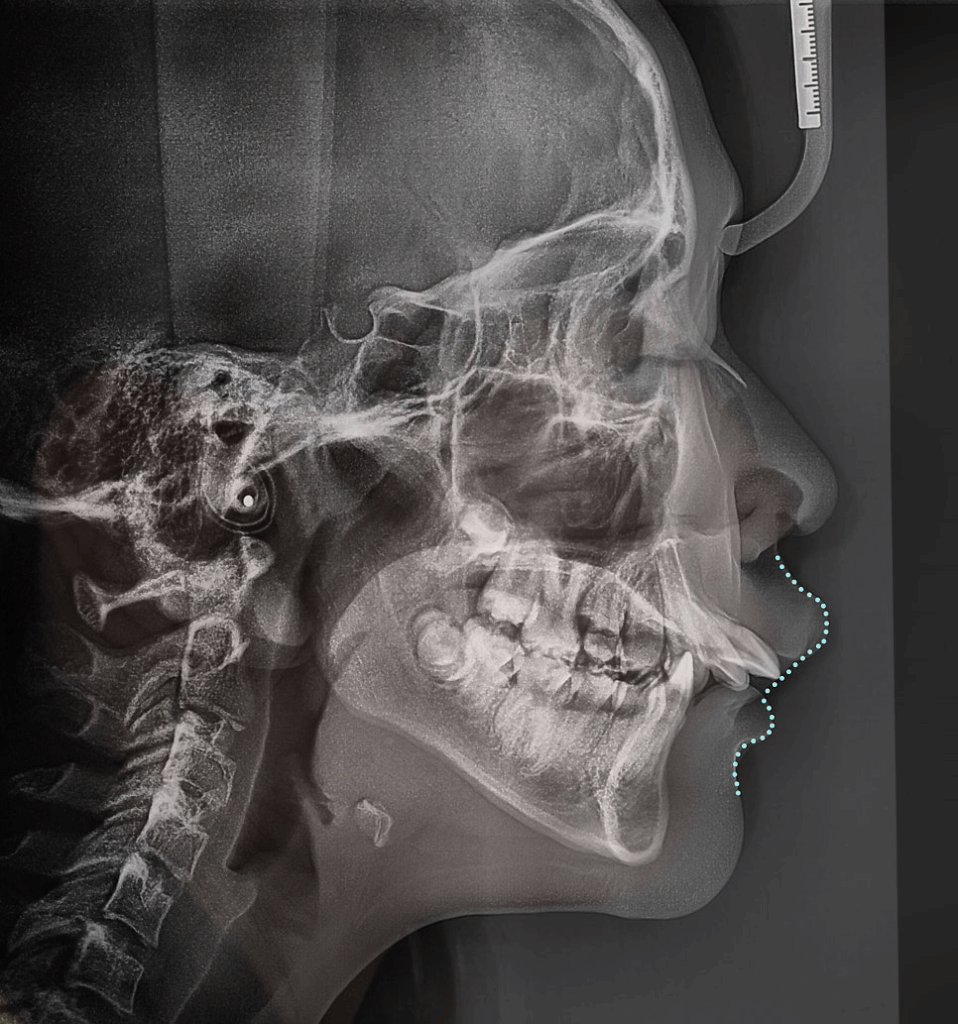

위 사진처럼,

위턱뼈가 앞으로 돌출되었을 때

상악 성장을 막기 위해 사용되고 있습니다.

즉, 위턱뼈가

앞으로 자라지 못하도록

뒤로 당겨주는 역할을 하게 되는데요.

위턱은 자라지 못하고

아래턱은 계속해서 자라기 때문에

자연스레 돌출감이 해소됩니다.

이번 케이스는

‘위턱이 많이 나온 상황’으로

측절치의 결손으로

위턱과 아래턱의 부조화가 나타났습니다.

이를 해결하려면,

위턱을 뒤로 밀어 넣어야 했기 때문에

헤드기어 를 활용해 교정을 진행하기로 했습니다.